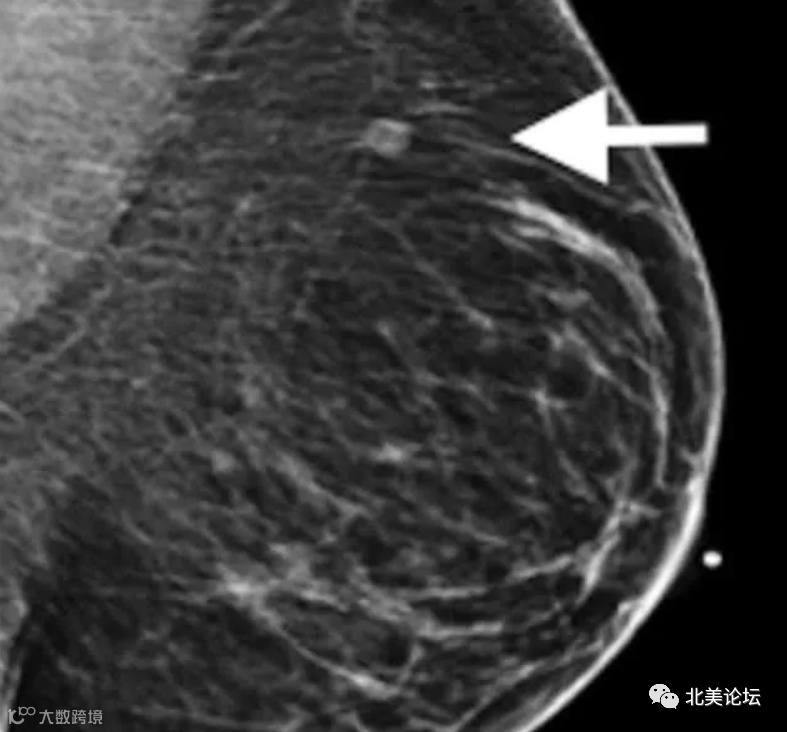

除此之外,癌症研究人员需多加注意,因为这或许会致使错误的癌症诊断。对此,相关机构官员建议五十岁之上的女性,能够在接打辉瑞疫苗前或是接打完疫苗后6个星期做乳房X光检测,以避免把辉瑞疫苗的副作用错误地解读成为癌症。